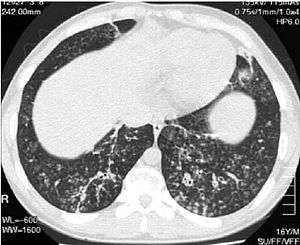

| High resolution computed tomography images of the lower chest in a 16-year-old boy with diffuse panbronchiolitis | |

The diagnosis of DPB requires analysis of the lungs and bronchiolar tissues, which can require a lung biopsy, or the more preferred high resolution computed tomography (HRCT) scan of the lungs.[7] The diagnostic criteria include severe inflammation in all layers of the respiratory bronchioles and lung tissue lesions that appear as nodules within the terminal and respiratory bronchioles in both lungs.[4] The nodules in DPB appear as opaque lumps when viewed on X-rays of the lung, and can cause airway obstruction, which is evaluated by a pulmonary function test, or PFT.[6] Lung X-rays can also reveal dilation of the bronchiolar passages, another sign of DBP. HRCT scans often show blockages of some bronchiolar passages with mucus, which is referred to as the "tree-in-bud" pattern.[7] Hypoxemia, another sign of breathing difficulty, is revealed by measuring the oxygen and carbon dioxide content of the blood, using a blood test called arterial blood gas. Other findings observed with DPB include the proliferation of lymphocytes (white blood cells that fight infection), neutrophils, and foamy histiocytes (tissue macrophages) in the lung lining. Bacteria such as H. influenzae and P. aeruginosa are also detectable, with the latter becoming more prominent as the disease progresses.[4][5] The white blood, bacterial and other cellular content of the blood can be measured by taking a complete blood count (CBC). Elevated levels of IgG and IgA (classes of immunoglobulins) may be seen, as well as the presence of rheumatoid factor (an indicator of autoimmunity). Hemagglutination, a clumping of red blood cells in response to the presence of antibodies in the blood, may also occur. Neutrophils, beta-defensins, leukotrienes, and chemokines can also be detected in bronchoalveolar lavage fluid injected then removed from the bronchiolar airways of individuals with DPB, for evaluation.[4][9]